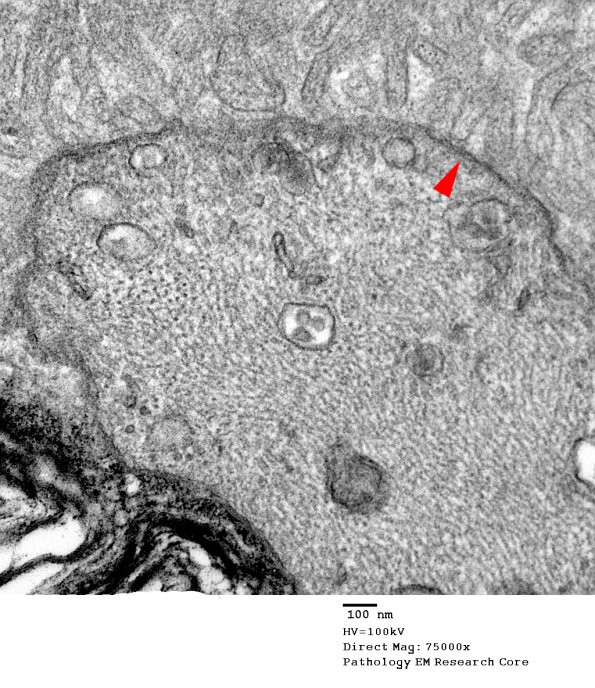

Many nodes may be asymmetrically cut and produce a questionable nodal appearance but the increased thickness of the axolemma (arrowhead), microvilli and increase in axonal organelles is evidence for its presence. (electron micrographs)